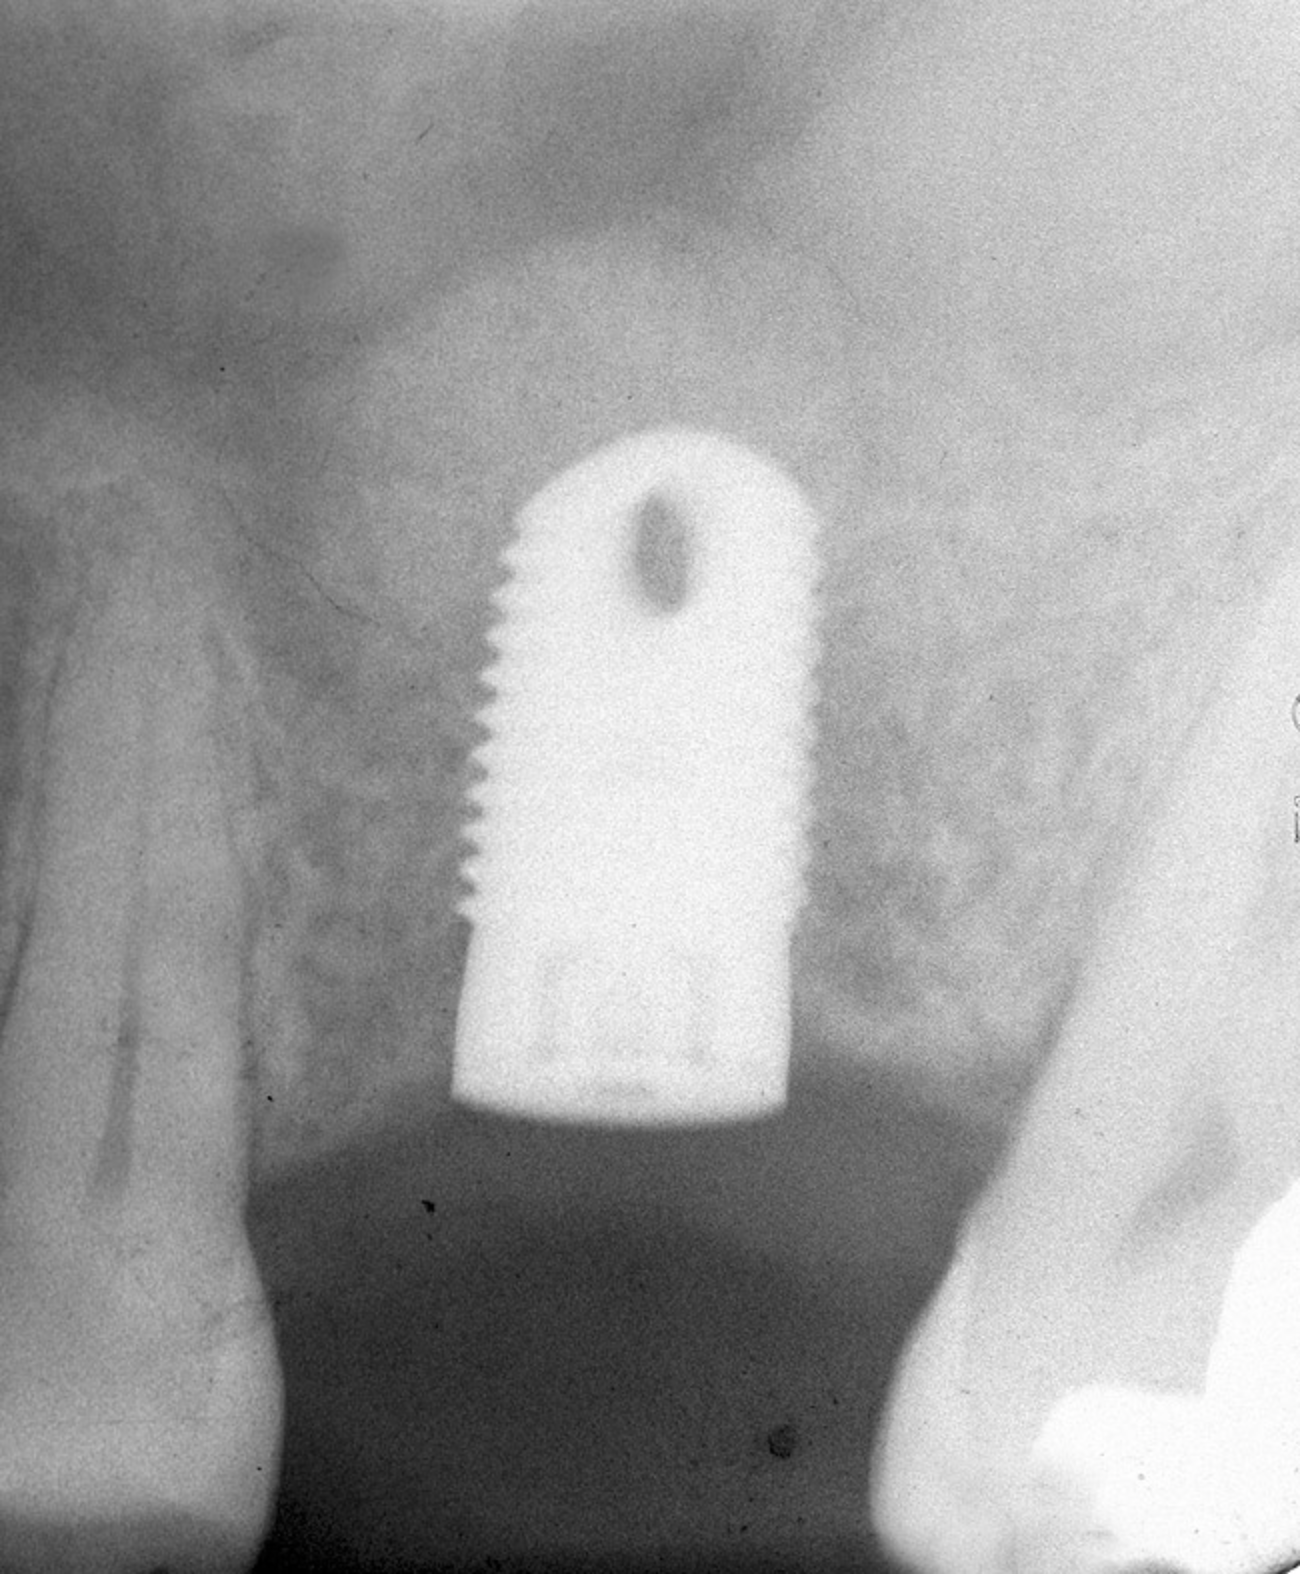

If the final osteotome employed was 3.5 mm, the size of the implant that can be placed should be 4.1-mm diameter or larger depending on the width of the ridge. Several factors should be considered when selecting the width of the inserted implant. If the height is relatively short (eg, 8 mm), a wider implant such as a 4.8-mm diameter will provide 30% more surface area than a 4.1-mm diameter implant (Figure 5).24 In addition, the wider implant will provide additional stability, especially if hand use of osteotomes caused some irregularities of the osteotomy site.

Figure 5  Insertion of a 4.8-mm implant, which fit snugly and increased the surface area for future osseointegration.

Figure 5

Figure 11  Insertion of a 4.8-mm implant, which fit snugly and increased the surface area for future osseointegration.

Figure 11